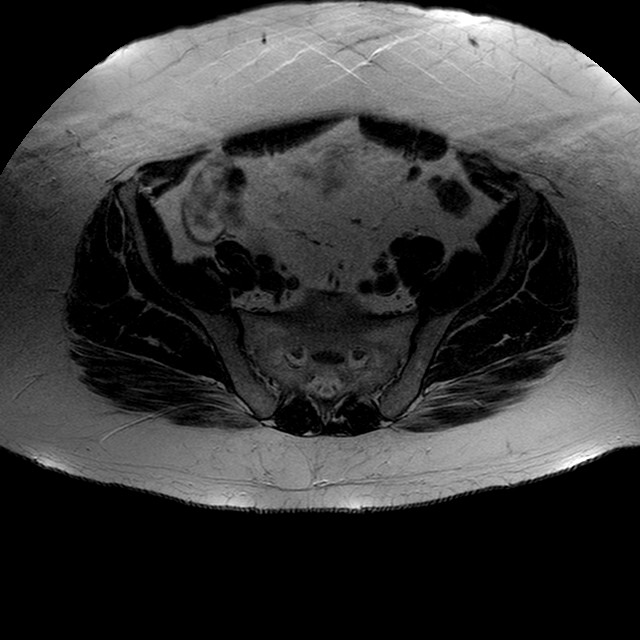

Esami: RMN BACINO

T2w TSE

Evidenti e simmetriche alterazioni osteofitosiche in regione coxo femorale con riduzione delle rime articolari. Degenerazione completa del cercine glenoideo. Non attuali segni di versamento articolare. Non segni di edema osseo che escludono attuale algodistrofia od osteonecrosi. Lieve e simmetrica riduzione del trofismo della muscolatura glutea.